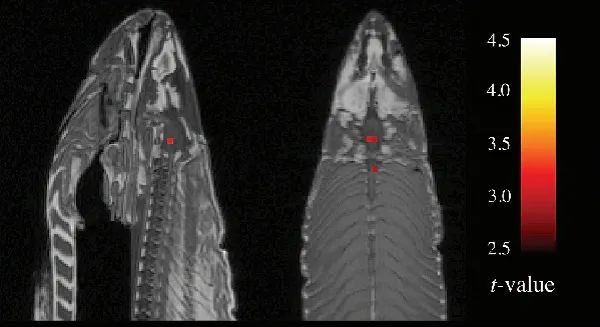

这个令人难忘的针对功能磁共振成像技术(fMRI)的驳斥出现在一次神经科学会议上。

fMRI能够帮助神经科学家探索哪些大脑区域参与了哪些认知,典型的研究会比较对象和对照组的fMRI图像,并思考为什么大脑的某些部分亮度有所不同。

但是,实验软件必须对评估结果的统计学意义做出假设。而最近的一项研究表明,这些假设有时会严重夸大差异。问题已经暴露,但科学家们并未对这个问题的严重性达成一致。

于是一份标题为《通过死大西洋鲑鱼研究人类神经活动:论多重比较校正的重要性》的学术墙报登场了。你没看错:一条死鲑鱼

这是一个故意为之的愚蠢实验。研究人员跟那条死鱼交谈,还给它看了人们在不同社交环境中的照片。结果令人震惊。当鲑鱼被问及人们的情绪时,影像显示它脑干的几个区域表现出来的活跃性高于它在“休息”时的活跃性。

这还只是对人类社交场景的“反应”,想象一下,如果这条鲑鱼被问及鲑鱼的情绪,这些区域会多么明亮。

要么是我们在死鱼认知方面取得了惊人发现,要么是我们未经修正的统计方法出了问题。